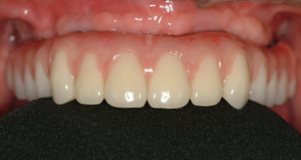

2.歯の形はほぼ天然歯があった時と同じになるので取り外しの義歯に比べて違和感がなく、手入れもインプラントの本数を少なくすることにより、清掃もし易くなっています。

3.インプラントの本数を少なくできることは、経済的も優れています。従来の治療では、無歯はでは10〜14本のインプラントを埋入していたのでそれと比較すると、かなりの治療費を削減できると考えます。